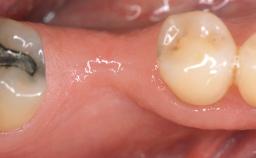

A 30-year-old woman was referred by her general dentist for evaluation of an esthetic complication related to previous implant treatment for congenitally missing maxillary lateral incisors. The patient’s chief complaint was the inadequate esthetic appearance of her smile. The case demonstrates the use of a combined approach to achieve optimal results. Two different flap designs - a tunnel technique and a coronally advanced flap - are employed based on the surgical objectives for the affected site.

Soft Tissue Grafting Yes

Soft Tissue Anatomy Intact Defective